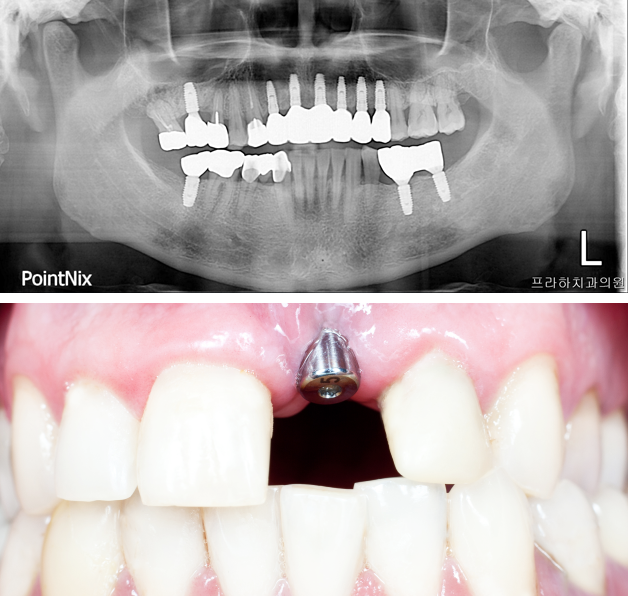

BONE GRAFT CASE

뼈이식은 임플란트가 튼튼하게 자리 잡을 수 있도록 하기 위해서는 꼭 필요한 과정입니다.

프라하치과는 이식 수술 후 빠른 재생을 돕기 위한 기술력을 더했습니다.